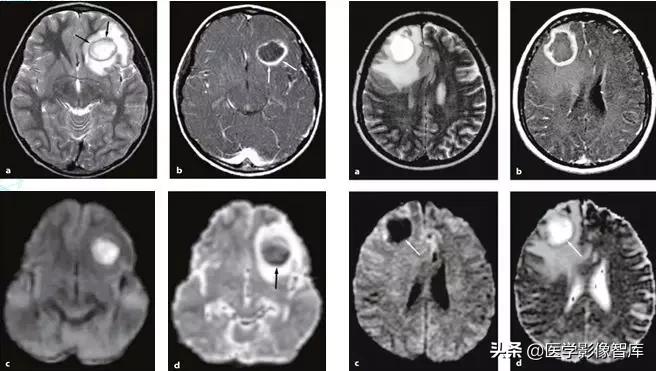

脑炎(包括病毒性脑炎、自身免疫性脑炎等)都有可能出现累及皮层 / 皮层下的 DWI 高信号。脑炎一般不难鉴别,急性起病,有发热、头痛等症状。累及皮层的脑炎会出现癫痫发作、精神症状等,行腰穿查脑脊液常规、生化、病毒抗体、自身免疫性脑炎抗体等可帮助诊断,图 1 为单疱脑炎患者发病 6 天时的磁共振检查结果。

图 1 单疱脑炎,起病 6 天,可见两侧颞叶病灶,右侧为甚,T2WI、FLAIR、DWI 均为高信号,ADC 图为低信号

对于有明确癫痫发作病史的患者,癫痫介导的脑部影像学改变需要考虑,不同于癫痫的病因(肿瘤、FCD 等),癫痫介导的脑部影像学改变往往是可逆的,磁共振上大多表现为 T2WI 高信号,约半数表现为 DWI 高信号,常见的受累部位包括皮层 / 皮层下、基底节区、白质、胼胝体、小脑,而临床上无其他特异性的表现,如图 2 所示。

图 2 42 岁女性,延长的亚临床癫痫持续状态患者所做的两次头颅 MR 结果。A 为 T2WI,B、C、F 为 DWI,D 为 ADC 图,E、G 为 FLAIR,可见发病 4 天时双侧顶枕叶可见明显 DWI 高信号病灶,T2 相也为高信号,ADC 低信号,发病 25 天时,病灶消失

克雅病(CJD,Creutzfeldt–Jakob disease)是由朊蛋白病毒所致的一类具有传染性、进行性恶化的神经系统变性疾病,主要表现为进行性痴呆、精神障碍、肌阵挛等。病程后期脑电图可见特异性的三相波,部分患者脑脊液 14-3-3 蛋白阳性。此种病目前为止没有任何有效的治疗方式,患者在出现临床症状后一般在半年至两年内死亡。CJD 早期无影像异常,中晚期常出现一些影像异常,比较典型的有花边征(cortical ribbon,又叫飘带征,特点即为皮质 DWI 高信号,常见于散发型 CJD),曲棍球征(hockey-stick sign,指双侧丘脑枕和背内侧丘脑同时对称性受累的 T2、DWI 高信号病变,常见于变异性 CJD)。临床上,进行性痴呆、椎体 / 椎体外系症状、脑电图异常(三相波)患者若出现花边征,常常指向 CJD。图 3 显示一个散发型 CJD 患者磁共振检查结果。

图 3 花边征(飘带征),散发型 CJD 患者,A、B 为 DWI,C 为 ADC 图,D 为 FLAIR。可见患者双侧皮层不对称的 DWI 高信号(箭头),基底节区 DWI 高信号(三角箭头),病灶 ADC 图上为低信号,FLAIR 上高信号

线粒体脑肌病是一组累及多系统的复杂疾病,伴有广泛的生化和遗传缺陷。线粒体脑肌病伴高乳酸血症和卒中样发作(MELAS)是研究相对较多的一类线粒体脑肌病。卒中样发作是 MELAS 的主要临床特征。尽管 MELAS 卒中样发作常在病程早期快速而完全的恢复,可是一旦第一次卒中样发作发生,患者的神经功能状态会持续恶化。卒中样发作在临床上可表现为多种神经系统症状,如癫痫发作、头痛、意识状态改变、局灶性无力、视力下降、感觉缺失、构音障碍和共济失调。典型的 MELAS 磁共振病变多分布在皮质和皮质下白质,深部白质不受累,表现为 T2WI、DWI 高信号类似卒中样表现。磁共振波谱可检测到梗死灶及其他脑部未受累区域中乳酸的存在。典型磁共振表现如图 4 所示。

图 4 MELAS 患者,A 为 DWI,可见皮层 / 皮层下 DWI 高信号,B 为 ADC 图,可见病灶低信号,C 为 FLAIR,可见病灶高信号,D 为该患者的慢性期 FLAIR,可见病灶几乎消失,受累部分脑策划萎缩